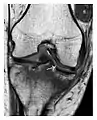

The greater tuberosity of the humerus is also an illustrative location of occult fractures. The osseous injury may follow seizures, glenohumeral dislocation, forced abduction, or direct impaction. They are commonly discovered on MRI in symptomatic patients with suspicion of rotator cuff tear. Coronal images are best suited for detection. They appear as crescentic oblique lines surrounded by a bone marrow edema pattern (Figure 5). The rotator cuff must be inspected since associated ligamentous lesions are common. In the ankle, malleoli and tarsal bones should be checked carefully for any cortical disruptions and radiolucent lines that may reveal a fracture. Awareness of the exact location of the pain will help direct the attention of the interpreter when searching for very subtle signs of fracture (Figure 6).[1]

a

b

Figure 6: Subtle anterior talar fracture in a 39-year-old man presenting with ankle pain after a fall. (a) Anteroposterior radiograph shows a subtle oblique radiolucent line through the talus (white arrows). (b) Sagittal CT reformation confirms the presence of an anterior talar fracture with cortical offset (black arrow). Avulsion fractures, which consist of a detached bone fragment resulting from a ligament or tendon pulling away from the bone, may also present with subtle radiographic signs. Tiny osseous fragments near the presumed attachment site of a ligament suggest this diagnosis. Common sites are the lateral tibial plateau (the Segond fracture), the spinal tuberosity of the tibia resulting from anterior cruciate ligament avulsion, and the ischial tuberosity.[1]